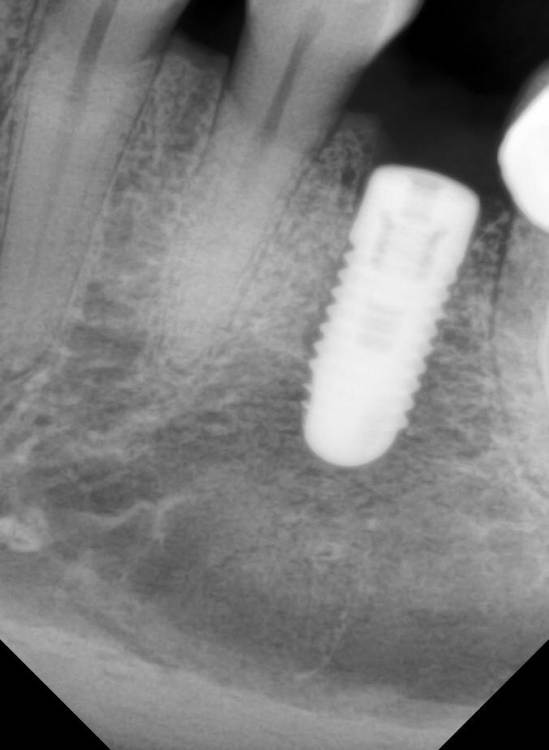

Панорама до удаления и установки импланта. Прицельные сделали вчера до депульпирования 34.

Зуб 3.5, а не 4.6, понять по снимку немецкий или нет сложно (желательно знать конкретную марку), по снимкам ничего криминального нет, но если причина болей в импланте то снимки ещё недели две ничего и не покажут.

Решение о депульпировании принимается скорее на основании клинического осмотра, снимки тут имеют вспомогательное значение

судя по предоставленным снимкам явных причин депульпировать 3.4 зуб я не вижу